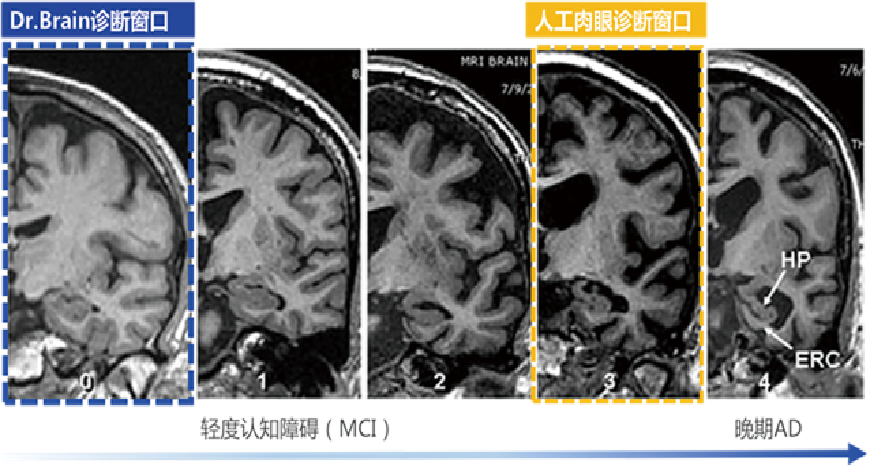

脑医生针对AD诊断,测量海马体积、脑室体积、侧脑室体积、颞叶体积等指标,并且所有指标针对颅内体积进行标准化,目前系统对阿尔兹海默症的临床诊断准确率已高达到96.30%,敏感性为93.55%,属国内外的高诊断水平,媲美医学专家手动勾画。脑医生将AD诊断窗口较传统人工阅片诊断方法提前10年。同时,脑医生的AI预测算法,能够预测病人患有AD,从轻度认知障碍(MCI)到AD转化的可能性,为临床决策提供重要的参考信息。